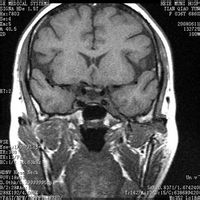

席汉氏综合症(Sheehan),按疾病分类属于内分泌科。脑下垂体前叶分泌很多促激素,如促性腺激素,促甲状腺素,促肾上腺皮质激素,泌乳素,生长激素等。脑垂体前叶与下丘脑之间有门静脉联系,接受下丘脑分泌的神经多肽物质。产后大出血容易引起这些门静脉发生血栓,最终导致脑下垂体前叶发生坏死,各种促激素水平大大降低,于是发生甲状腺,肾上腺皮质,卵巢等功能减退,乃至出现前面所讲的各种症状,这是一种严重的疾病,重要的是预防产后出血,一旦产后大出血,就应及时补充循环血容量,避免休克的发生。